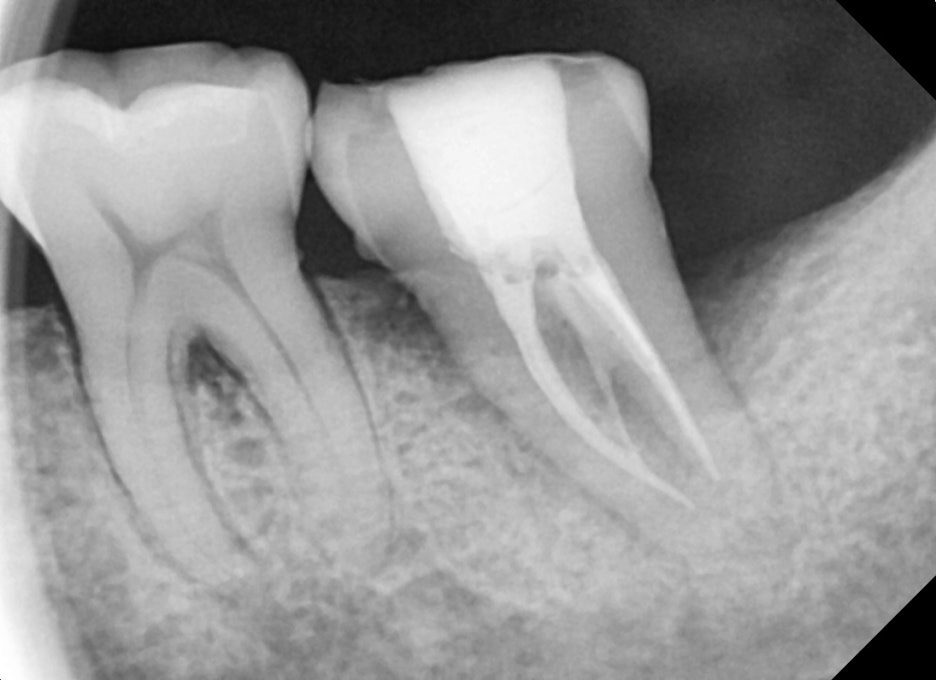

바른영치과 신경치료 전후 사례

3단계는 상아질 내부에 있는 신경까지 충치가 침습한 경우입니다. 이 때는 특별한 자극이 없어도 치통이 느껴지고 이 시림 증상이 있어 일상생활에 지장이 생기기 시작합니다. 이 때는 레진, 인레이 만으로는 치료가 어렵고 충치가 침범해 염증이 생긴 치수 즉 신경을 제거한 후 보충재를 채운 후 크라운을 씌워주는 치료를 진행하게 되며, 이 단계가 자연치아를 살릴 수 있는 마지막 단계입니다.